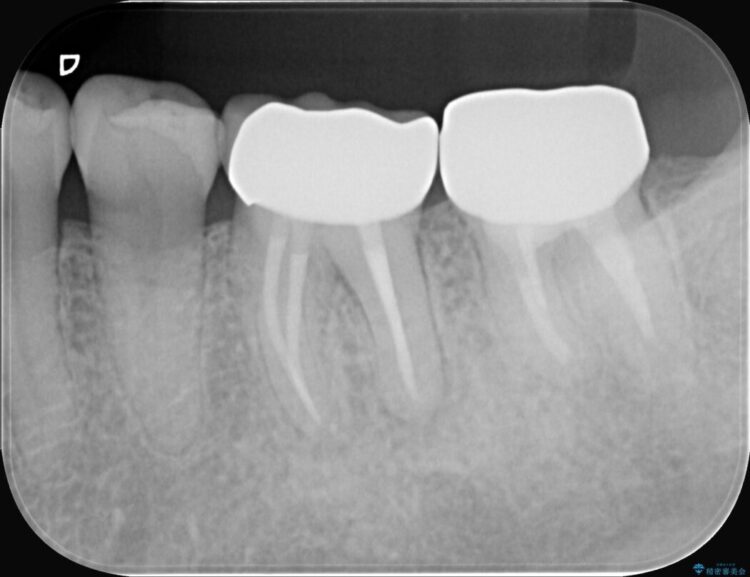

詰め物内部の虫歯治療、隠れた根管の発見

詰め物内部の虫歯治療、隠れた根管の発見 ビフォー 詰め物内部の虫歯治療、隠れた根管の発見 アフター

奥歯の詰め物が取れたとご来院された患者様です。